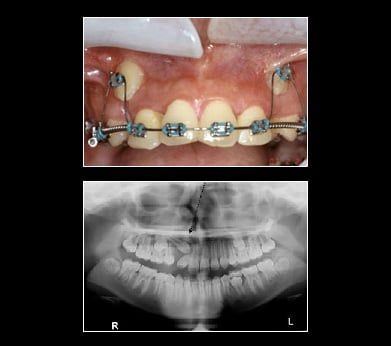

Treatment for Impacted Canines

After assessing your situation, Cervantes & Prado Dental Care Inc will devise a plan to make room for your canines. Will a typical oral surgery and the assistance of an orthodontist your canine will find their way into their proper place over time.